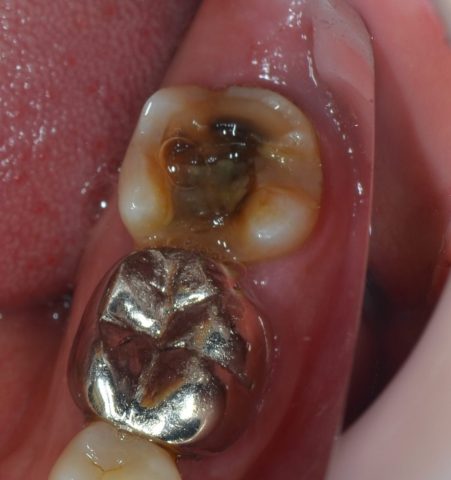

↓被せ物を取ってみると…中が黒くなっています。

実際のお写真がこちらです。↓↓

被せ物の中で虫歯が進行していたため中が黒くなっています。